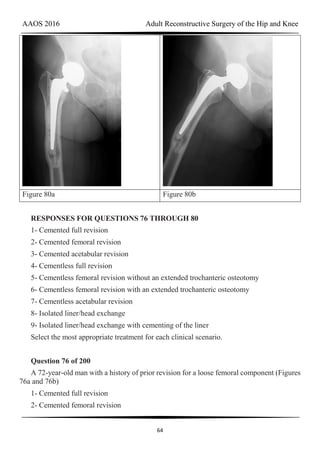

the acetabular component or postsurgical noningrowth of the component. Although scarring

from radiation may put the hip at increased risk for arterial or nerve damage or infection, this

risk has not been associated with pelvic radiation. Cementless acetabular components with

porous metal surfaces such as trabecular metal should be considered.

Question 144 of 200

A 24-year-old man has bilateral hip pain. An examination and imaging studies (plain

radiographs and MR imaging) confirm evidence of femoroacetabular impingement (FAI) with

a CAM deformity in both hips. The patient mentions that he has a 19-year-old brother who has

occasional hip pain. With respect to his brother’s pain, how should you counsel the patient?